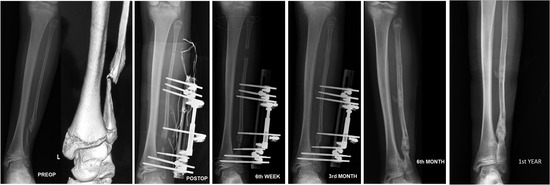

Treatment of Recalcitrant Isolated Congenital Fibular Pseudarthrosis: Fibular Segment Transfer and Tibiofibular Synostosis with Unilateral External Fixator

Isolated congenital pseudarthrosis of the fibula is a rare entity with a limited number of cases reported in the literature. Treatment is challenging because of recalcitrant nonunion and because no consensus about the best treatment plan exists. We report a case of isolated [...] Read more.

Isolated congenital pseudarthrosis of the fibula is a rare entity with a limited number of cases reported in the literature. Treatment is challenging because of recalcitrant nonunion and because no consensus about the best treatment plan exists. We report a case of isolated congenital fibular pseudarthrosis with valgus deformity of the ankle. The patient had a history of two failed operations. We used a novel surgical plan that combined tibiofibular synostosis with fibular segment transfer through a unilateral external fixator. The patient showed good early results with fibular union. We advocate the combination of tibiofibular synostosis and fibular segment transfer to restore the integrity and stability of the ankle in recalcitrant isolated congenital fibular pseudarthrosis cases with a history of failed surgery. Full article